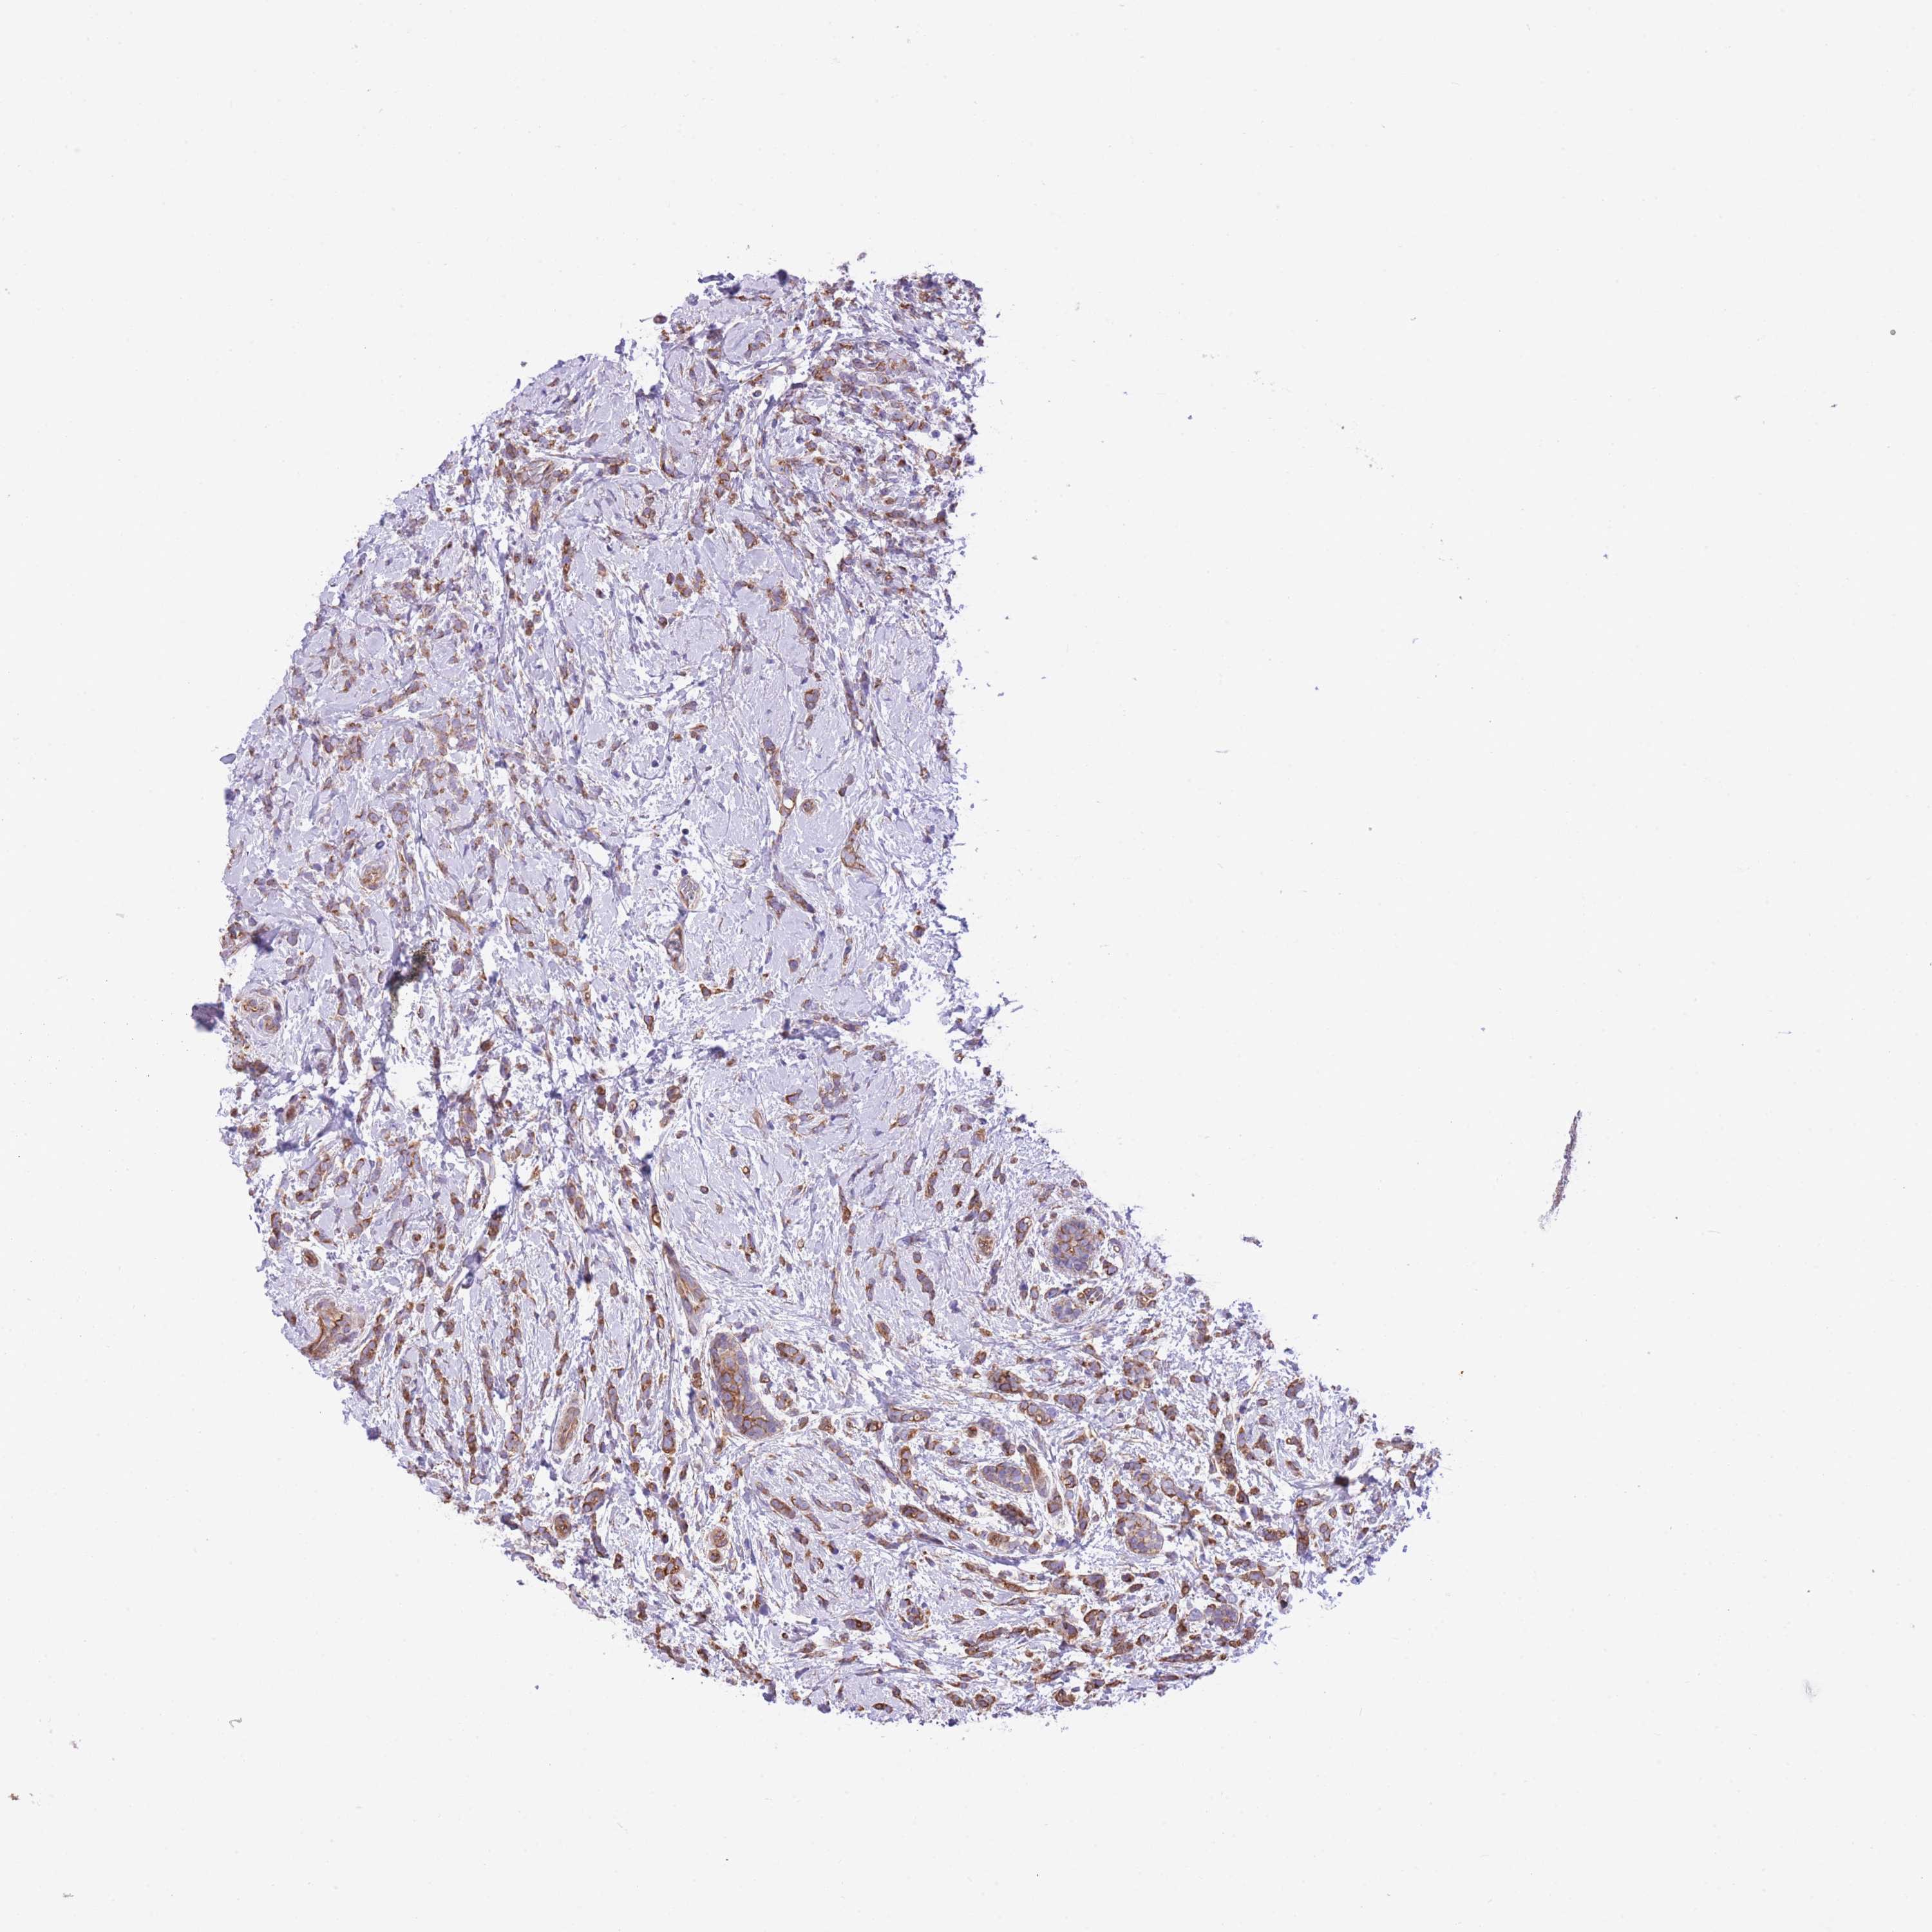

CANCER BREAST CANCER Show tissue menu

Breast cancer

Human cancer